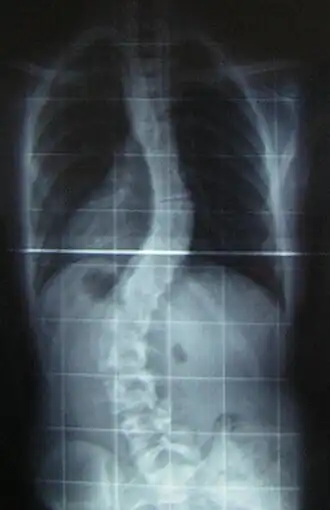

![]() Рентгеновский снимок позвоночника пациента со сколиозом с левосторонним искривлением в поясничном отделе и правосторонним искривлением в грудном отделе позвоночника. | |

Сколио́з (лат. scoliōsis ← греч. σκολιός «кривой») — трёхплоскостная деформация позвоночника у человека. Искривление может быть врождённым, посттравматическим и идиопатическим (т.е. "неизвестнопричинным").

Величина искривления позвоночника измеряется с помощью рентгеновского снимка всего позвоночника стоя. Возможны и врождённые рёберные деформации и деформации тел позвонков. С помощью этой информации можно отличить идиопатический и врождённый сколиоз. На рентгеновском снимке в боковой проекции можно также определить, есть ли врождённые деформации в этой плоскости или нарушения нормальных изгибов позвоночника — физиологических кифозов и лордозов.

Схема анализа рентгеновского снимка для определения угла искривления разработана в 50-х годах XX века американским ортопедом Дж. Коббом (англ. John Robert Cobb). Угол искривления, измеренный по рентгеновским снимкам теперь называется «углом по Коббу». Для определения угла деформации на передне-задней рентгенограмме проводят две линии, параллельных замыкательным пластинкам нейтральных позвонков. В точке пересечения этих линий или перпендикуляров к ним измеряют угол сколиоза.